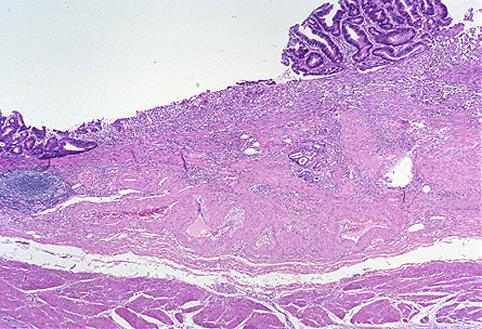

Criteria of Hist.ClassificationMalignant epithelial tumor/Adenocarcinoma

LocationStomach/Body

Technique, MethodHistology

Macroscopic TypesType 0/IIc (IIc) Superficial depressed type

Size15 - 19

Depth of Tumor Invasionsubmucosa